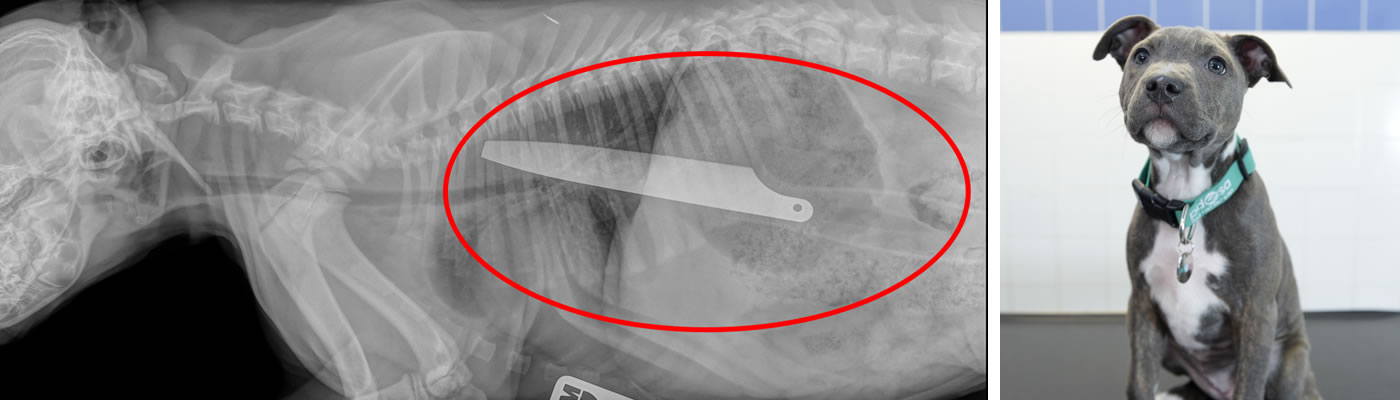

A kitchen knife

Macie’s x-ray has to be one of the most astonishing our vets have ever seen. She was rushed to us when she started chocking and being sick. An x-ray clearly showed the cause of the problem - Macie had somehow managed to swallow a 8 inch kitchen knife. Thankfully, the knife hadn’t caused any damage and she quickly recovered after an operation to (very carefully!) remove it.